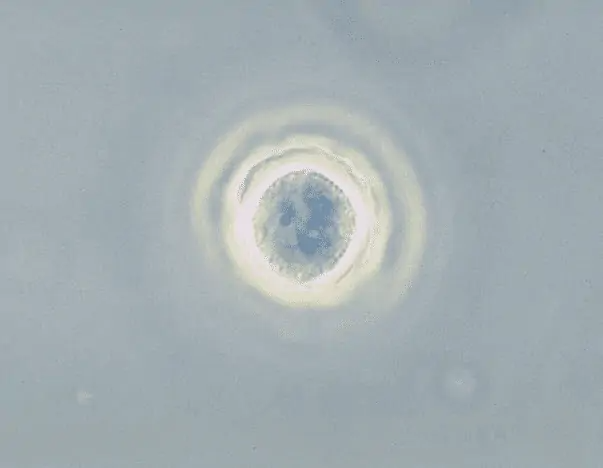

6. Acanthamoeba

Loại ký sinh trùng amip này gây ra bệnh viêm não amip có u hạt (GAE), một căn bệnh dẫn đến sưng não. Khoảng 95% bệnh nhân bị GAE bị amip giết. Tuy nhiên, không phải mọi người nhiễm Acanthamoeba đều bị GAE và một số bệnh nhân có thể không bao giờ xuất hiện bất kỳ triệu chứng nào.

Ký sinh trùng có thể được tìm thấy trong đất, bể bơi được khử trùng bằng clo, nước máy, trên bề mặt kính áp tròng, nước đóng chai và thiết bị điều hòa không khí và nó có thể xâm nhập vào cơ thể người qua mắt, vết loét, vết thương và hốc mũi.

Khi Acanthamoeba nhiễm vào mắt, tình trạng này được gọi là viêm giác mạc. Người mắc bệnh phải đối mặt với tình trạng đau mắt dữ dội, nhìn mờ, đỏ mắt, loét giác mạc và nhiều vấn đề liên quan đến mắt khác. Trong trường hợp này, chẩn đoán sớm là vô cùng quan trọng vì nếu không được điều trị, bệnh nhân có thể bị mù vĩnh viễn do nhiễm trùng.